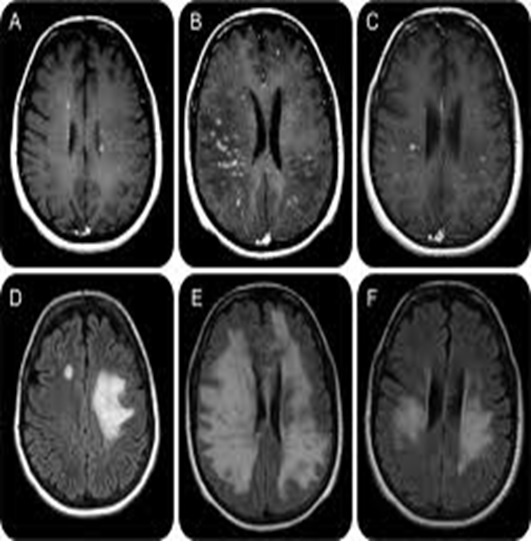

Multipl Skleroz (MS) merkezi sinir sisteminde pek çok yeri farklı ya da eş zamanlı olarak etkileyebilen bir hastalıktır. Hastalık; beyin ve omuriliğin hasarlı alanlarında sklerozan plaklar, yani sertleşmiş dokular oluşturur (RESİM 1). MS hastalığı daha çok 20 ila 40 yaşlar arasındaki yetişkinlerde görülmektedir. Daha erken veya daha ileri yaşlarda görülme olasılığı oldukça azalmaktadır.